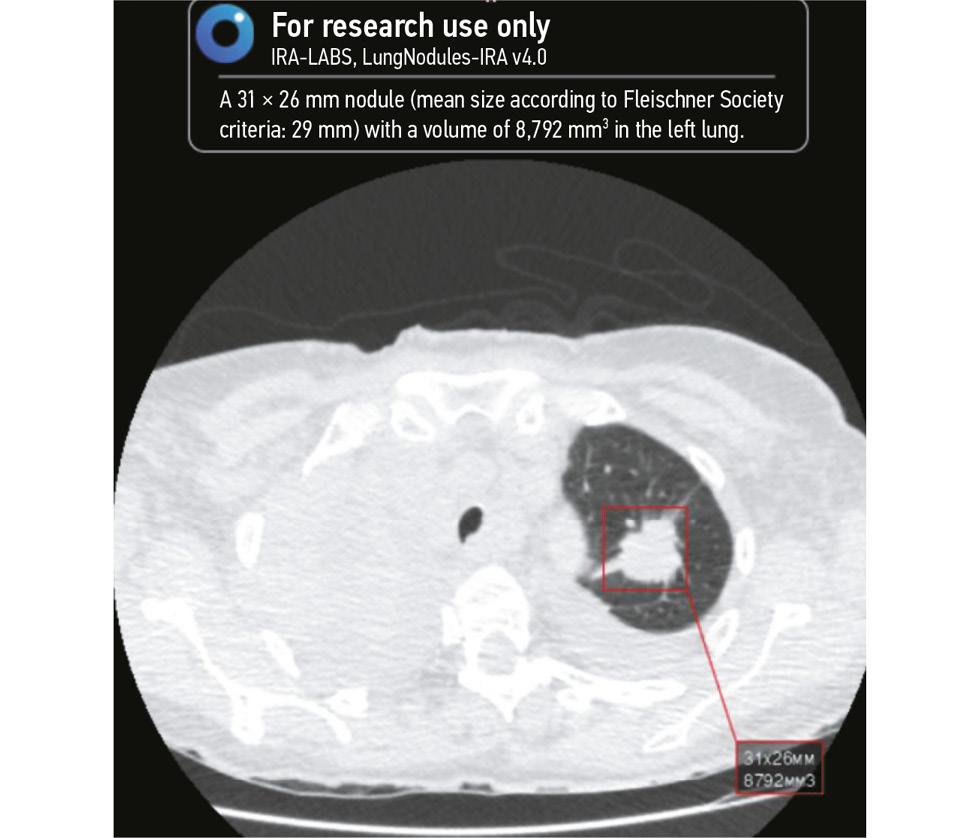

Fig. 3 and Fig. 4 illustrate the AI algorithm findings.

Fig. 3. Left lung nodule detected by artificial intelligence. The detected nodule is marked by the red square. Image with a high probability of lung cancer.